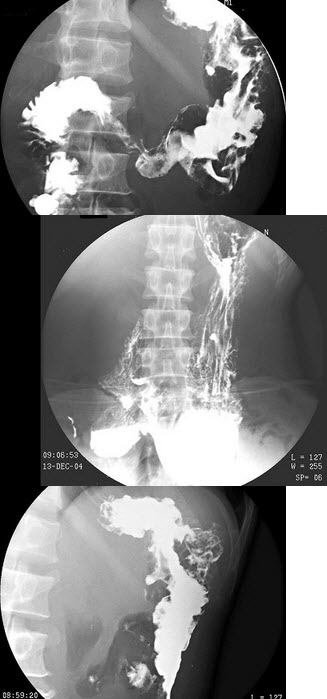

16、单项选择题

男,9岁,脸色苍白5月。上腹部不规则疼痛。大便潜血(+),血红蛋白61g/L,结合图像,最可能的诊断为()

A.正常表现

B.胃窦炎

C.球部溃疡

D.十二指肠球炎

E.球后溃疡